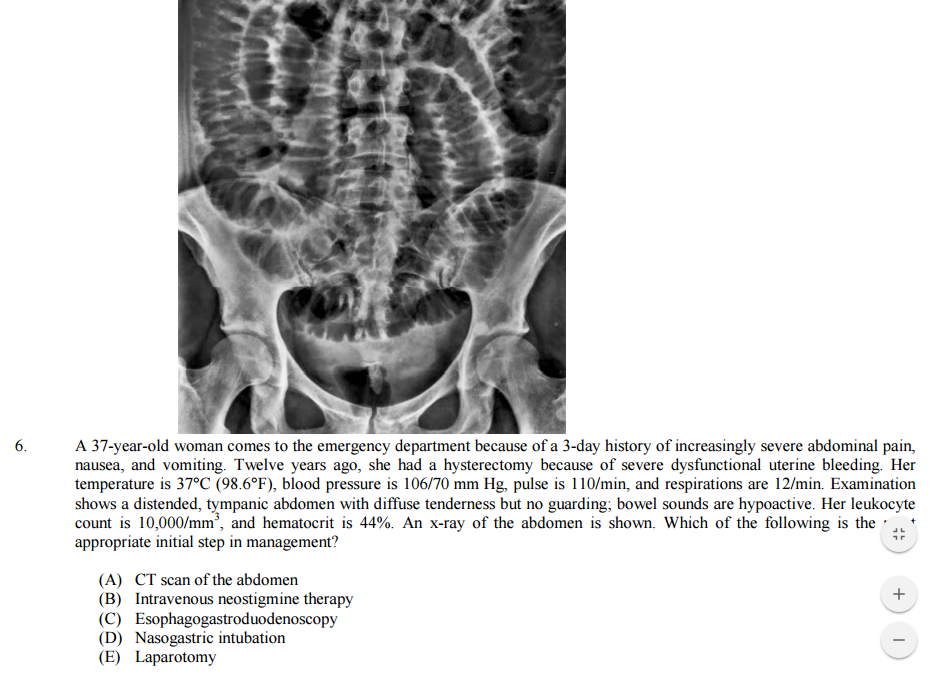

6. She has a partial small bowel obstruction, since she still has some bowel sounds. So go conservative first: IVF, NG tube to decompress, NPO. If it worsens or she goes peritoneal-->ex-lap.

6. SBO given XRay showing valvulae conniventes suggesting small bowel (vs. haustra which is large bowel). PianoMedic recs are appropriate. NG tube to decompress and remove remaining gastric contents, allowing bowel rest.

Note, SBOs often resolve by themselves so immediate/urgent surgery not recommended (vs. large bowel obstruction). Bowel sounds are not really that reliable. Hyperactive suggests obstruction, though late obstruction would result in hypoactive. Hypoactive on exams usually suggest ileus. Determine diagnosis by combining clinical presentation with exam findings.